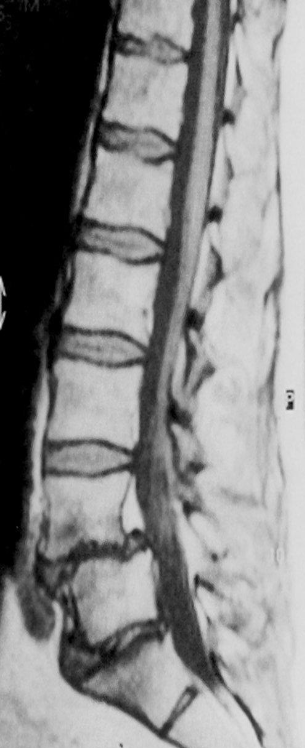

Modality MRI lumbar spine (sagittal plane)

Findings anterolisthesis of the L4 vertebral body

Diagnosis Spondylolisthesis